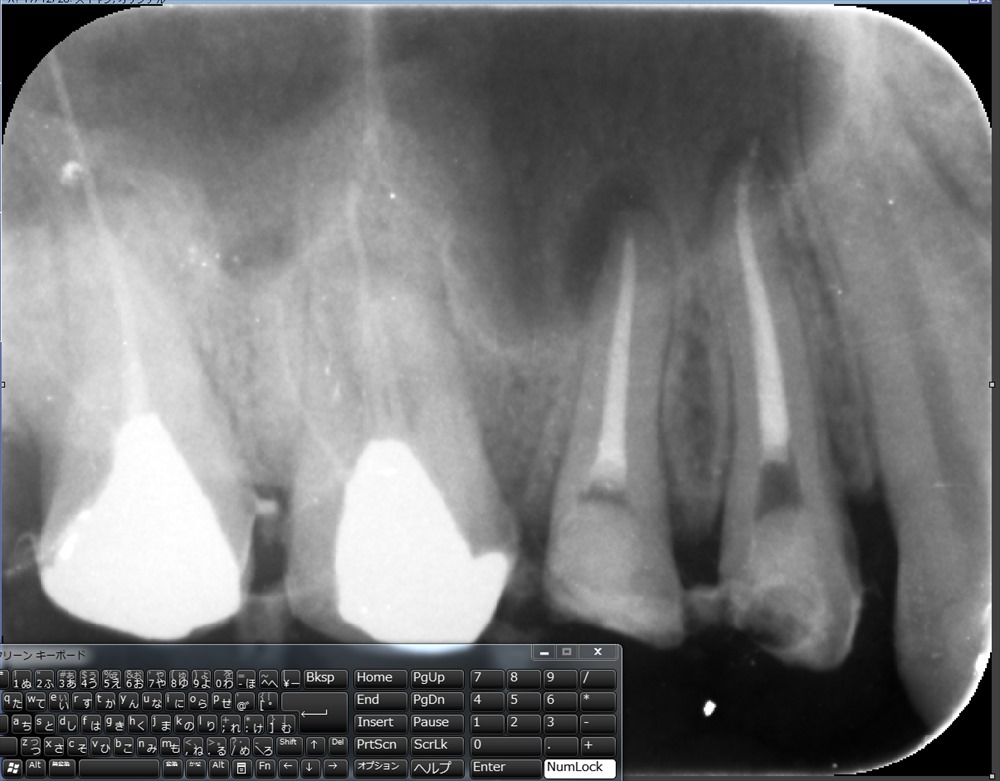

精密根管治療のケース。

前回スタート。グライドパスまで前回終了。

今回で根管形成終わり。イスムスの整理。

これで抜歯せずに済みますね!!Kさん。本当に良かった!!